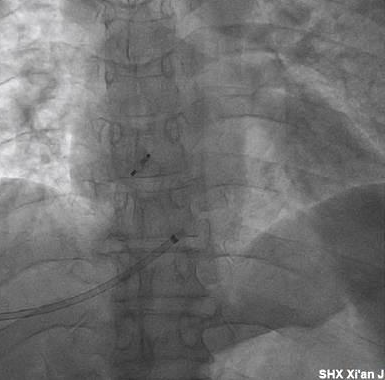

在做好周密的术前准备及应急预案后,4月6日下午17:30分,超声医学科魏炜教授凭借高超的技术与丰富的穿刺经验,在超声引导下对患者实施了精准肝静脉穿刺,整个穿刺过程快速、顺利、安全。

随后,魏峰副主任医师保留穿刺导丝后,护送患者到达介入手术室,在王海燕主任与肖娟护士长的统一协调下,介入手术室早已做好了准备,18:20分手术正式开始,在王海燕主任与张玉顺教授的指导下,何璐主治医师、王星烨主治医师、魏峰副主任医师密切协作,精准操作,李声波等介入护理团队紧密配合,一起顺利完成了经肝静脉PFO封堵术,随后消化内科马福权主治医师与魏峰副主任医师密切合作,顺利完成了经颈静脉穿刺路径对经皮肝静脉穿刺伤口的栓塞与封堵处理。整个手术过程历时两个半小时,手术安全、顺利。

术后患者恢复良好,术后第1天即可下床活动,复查心脏超声提示:封堵器形态、位置良好,房水平未见分流,复查肝脏超声提示:肝静脉血流通畅,肝脏穿刺口处理良好,未见出血。术后观察3天,患者活动后无任何不适,已于4月10日顺利出院。患者及家属对整个诊疗团队十分感激,不停地竖起大拇指说道:“感谢诊疗团队精湛的医术与高尚的医德,交大一附院真棒!”。